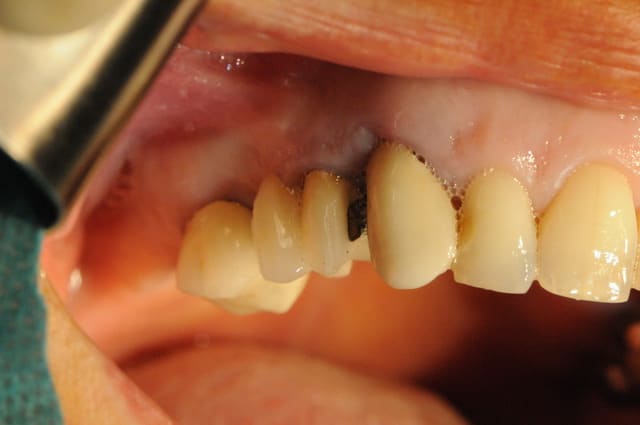

bien vu growly pour la récession distale de 12!

mais elle était hautement prévisible car perte osseuse importante et utilisation de membrane titane qui ne permet pas la RTG.

par chance, cette récession était fortement souhaitée pour corriger l'aspect esthétique du sourire.

donc le lambeau d'accès, bien que pas terrible n'avait pas énormément d'importance.

revoici les deux photos avant et après.